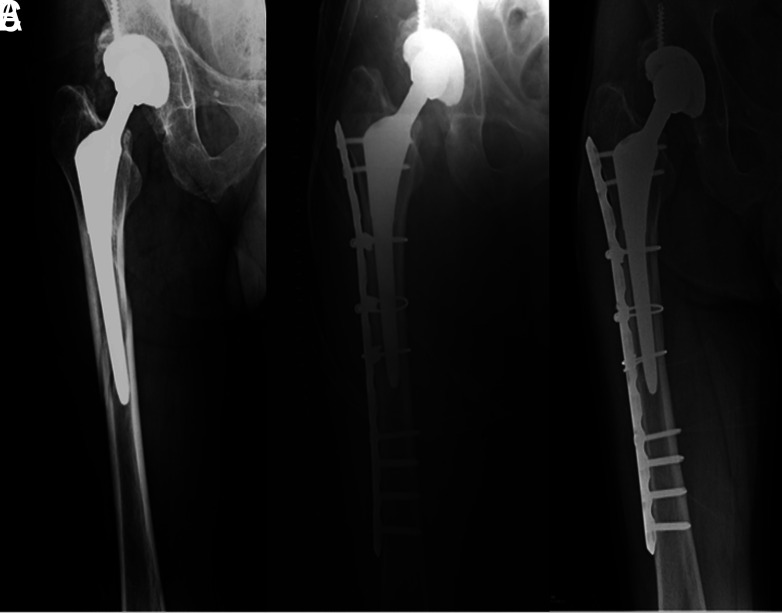

本研究旨在调查一家三级转诊中心连续收治的一组温哥华B1型和C型股骨假体周围骨折(PPF)患者中,使用混合锁定钢板/钢缆技术进行切开复位内固定术(ORIF)治疗的中长期手术效果。研究纳入了2005年至2016年期间诊断为温哥华B1型或C型股骨假体周围骨折并采用混合锁定钢板/钢缆技术治疗的25名患者(25例PPF;17名女性,8名男性)。根据患者最终随访时的哈里斯髋关节评分(Harris Hip Score,HHS),将患者的功能状态分为四组:70=效果差;70-80=一般;80-90=良好;90-100=优秀。术中和术后并发症也被记录在案。PPF愈合的临床定义是患者能够在有人或无人协助的情况下承受全部重量,X光片上的定义是出现与骨折桥接的胼胝。根据温哥华分类和HHS固定类型以及愈合时间进行了分组分析。初次髋关节置换时的平均年龄为 57 ± 16.6(17-82 岁)岁,PPF 时的平均年龄为 64 ± 18.7(24-88 岁)岁。从初次手术到PPF的平均随访时间为5.6±3.3(范围,2-14)年,PPF后的平均随访时间为6.5±4.1(范围,3-15)年。其中有 7 例 B1 型 PPF 和 18 例 C 型 PPF。在最后的随访中,平均 HHS 为 71 ± 7.74(范围为 57-89)。根据 HHS,8 名患者的功能效果较差,14 名患者的效果一般,3 名患者的效果良好。术中和术后均未发现重大并发症。所有患者平均在 13 ± 4.9 周(6-24 周)内实现骨折愈合,无并发症发生。在亚组分析中,虽然HHS没有观察到显著差异(温哥华类型的P=.87,固定类型的P=.96),但各组的骨折愈合时间不同。B1 型 PPF 的接合时间明显短于 C 型 PPF(P=.006)。与骨水泥固定组相比,非骨水泥固定组的骨结合时间要短得多(P=.017)。在锁定钢板上添加钢索可提供足够的稳定性,以保持骨折对位,实现温哥华B1型和C型PPF的骨性结合。虽然此类患者可通过ORIF实现骨结合,但在使用骨水泥股骨干或温哥华C型PPF的情况下,可能需要更长的骨结合时间。

This study aimed to investigate the mid-to-long-term surgical outcomes of open reduction and internal fixation (ORIF) using a hybrid locking plate/cable technique for the treatment of Vancouver type B1 and type C periprosthetic femoral fractures (PPFs) in a consecutive group of patients from a single tertiary referral center. Twenty-five patients (25 PPFs; 17 female, 8 male) in whom a Vancouver type B1 or type C PPF was diagnosed and treated by a hybrid locking plate/cable technique from 2005 to 2016 were included in the study. Patients' functional status was categorized into 4 groups based on the Harris Hip Score (HHS) at the final follow-up: 70=poor result; 70-80=fair; 80-90=good, and 90-100=excellent. Intraand postoperative complications were also recorded. PPF union was defined clinically as the patient's ability to bear full weight with or without assistance and radiographically as the presence of a callus bridging the fracture. Subgroup analyses were conducted according to the Vancouver classification and type of fixation regarding the HHS and time to union. The mean age was 57 ± 16.6 (range, 17-82) years at the time of the primary hip replacement and 64 ± 18.7 (range, 24-88) years at the time of PPF. The mean follow-up was 5.6 ± 3.3 (range, 2-14) years from primary procedure to PPF and 6.5 ± 4.1 (range, 3-15) years following PPF. There were 7 type B1 and 18 type C PPFs. At the final follow-up, the mean HHS was 71 ± 7.74 (range, 57-89). According to HHS, functional results were poor in 8 patients, fair in 14 patients, and good in 3 patients. No major intra- or postoperative complications were noted. Fracture union was achieved in all patients without complications at an average of 13 ± 4.9 (range, 6-24) weeks. In subgroup analysis, while no significant differences were observed in the HHS (P=.87 for the Vancouver type, P=.96 for the type of fixation), time to union differed among groups. Time to union was significantly shorter in type B1 than in type C PPFs (P=.006). Time to union was considerably shorter in the uncemented group compared to the cemented one (P=.017). Adding cables to the locking plate can provide adequate stability to preserve fracture alignment and achieve bony union in Vancouver type B1 and C PPFs. Although union can be achieved by ORIF in such patients, a longer union time may be required for PPFs in the setting of a cemented femoral stem or Vancouver type C. Level IV, Therapeutic study.